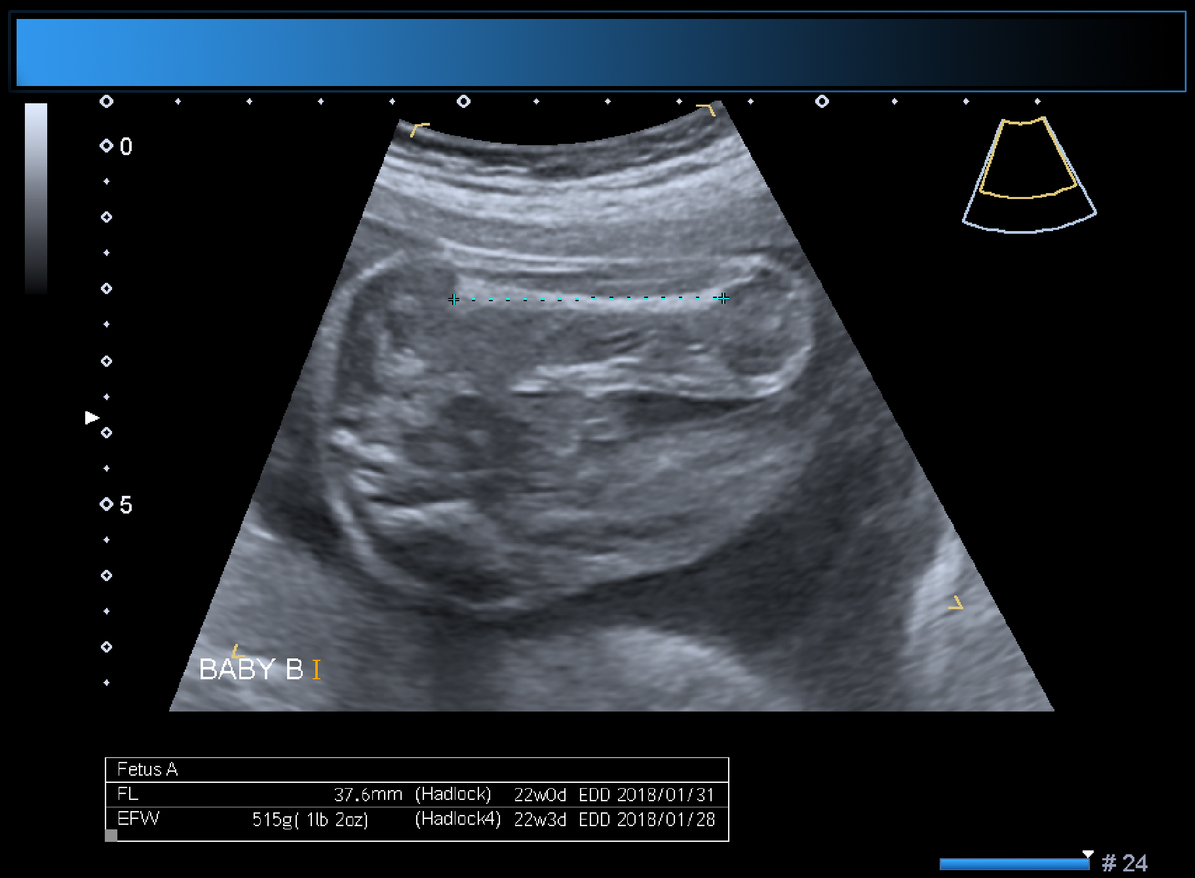

Anatomy scan of twin gestation 22 weeks 2 days, monochorionic diamniotic. Fetal anatomy visualized with normal appearance, kidneys, bladder, stomach. Male fetus genitalia. No fetal anomalies were detected. Partial posterior placenta previa.

Επισημαίνοντας ότι η Γ΄ Μαιευτική -Γυναικολογική Κλινική του ΑΠΘ είναι η μοναδική στη Βόρεια Ελλάδα όπου πραγματοποιούνται επεμβάσεις διαχωρισμού πλακούντα δίδυμων εμβρύων με σύνδρομο υποκλοπής και ότι σε διάστημα δύο χρόνων έγιναν περίπου επτά τέτοιες επεμβάσεις, ο κ. Αθανασιάδης εξηγεί: «Διαχωρισμό πλακούντα μονοχοριακών διδύμων με λέιζερ κάνουμε στην Κλινική μας εδώ και δύο χρόνια. Πολλές φορές όταν τα δίδυμα έμβρυα είναι μονοχοριακά, δηλαδή έχουν ένα πλακούντα τον οποίο μοιράζονται, το ένα έμβρυο «κλέβει» αίμα από το άλλο. Αυτό ονομάζεται σύνδρομο υποκλοπής από δίδυμο σε δίδυμο. «Κλέβει» σημαίνει ότι το ένα μεγαλώνει πάρα πολύ εις βάρος του άλλου, παίρνοντάς του το αίμα μέσω των αγγείων τα οποία αναστομώνονται μεταξύ τους. Ο μοναδικός λοιπόν τρόπος για να μπορέσουν να επιβιώσουν και τα δύο ή τουλάχιστον το ένα και να είναι χωρίς νευρολογικές παθήσεις, είναι να χωρίσουμε τον πλακούντα στα σημεία που ενώνονται μεταξύ τους. Με λέιζερ καίμε τις αναστομώσεις, δηλαδή χωρίζουμε τον πλακούντα στα σημεία των αναστομώσεων κι έτσι από πλευράς αγγείωσης χωρίζει ο πλακούντας. Είναι μία πολύπλοκη τεχνική η οποία γίνεται με εμβρυοσκόπιο. Στην Κλινική μας την επέμβαση αυτή κάνει ομάδα εξειδικευμένων μαιευτήρων-γυναικολόγων, οι οποίοι έχουν εκπαιδευτεί σε ειδικά κέντρα, με υπεύθυνο τον κ. Γεώργιο Παπαιωάννου. Στο διαχωρισμό που έγινε πριν λίγες ημέρες τα δίδυμα ήταν μονοχοριακά διαμνιακά, δηλαδή είχαν έναν πλακούντα και δύο σάκους και ήταν στην 21η εβδομάδα της κύησης».